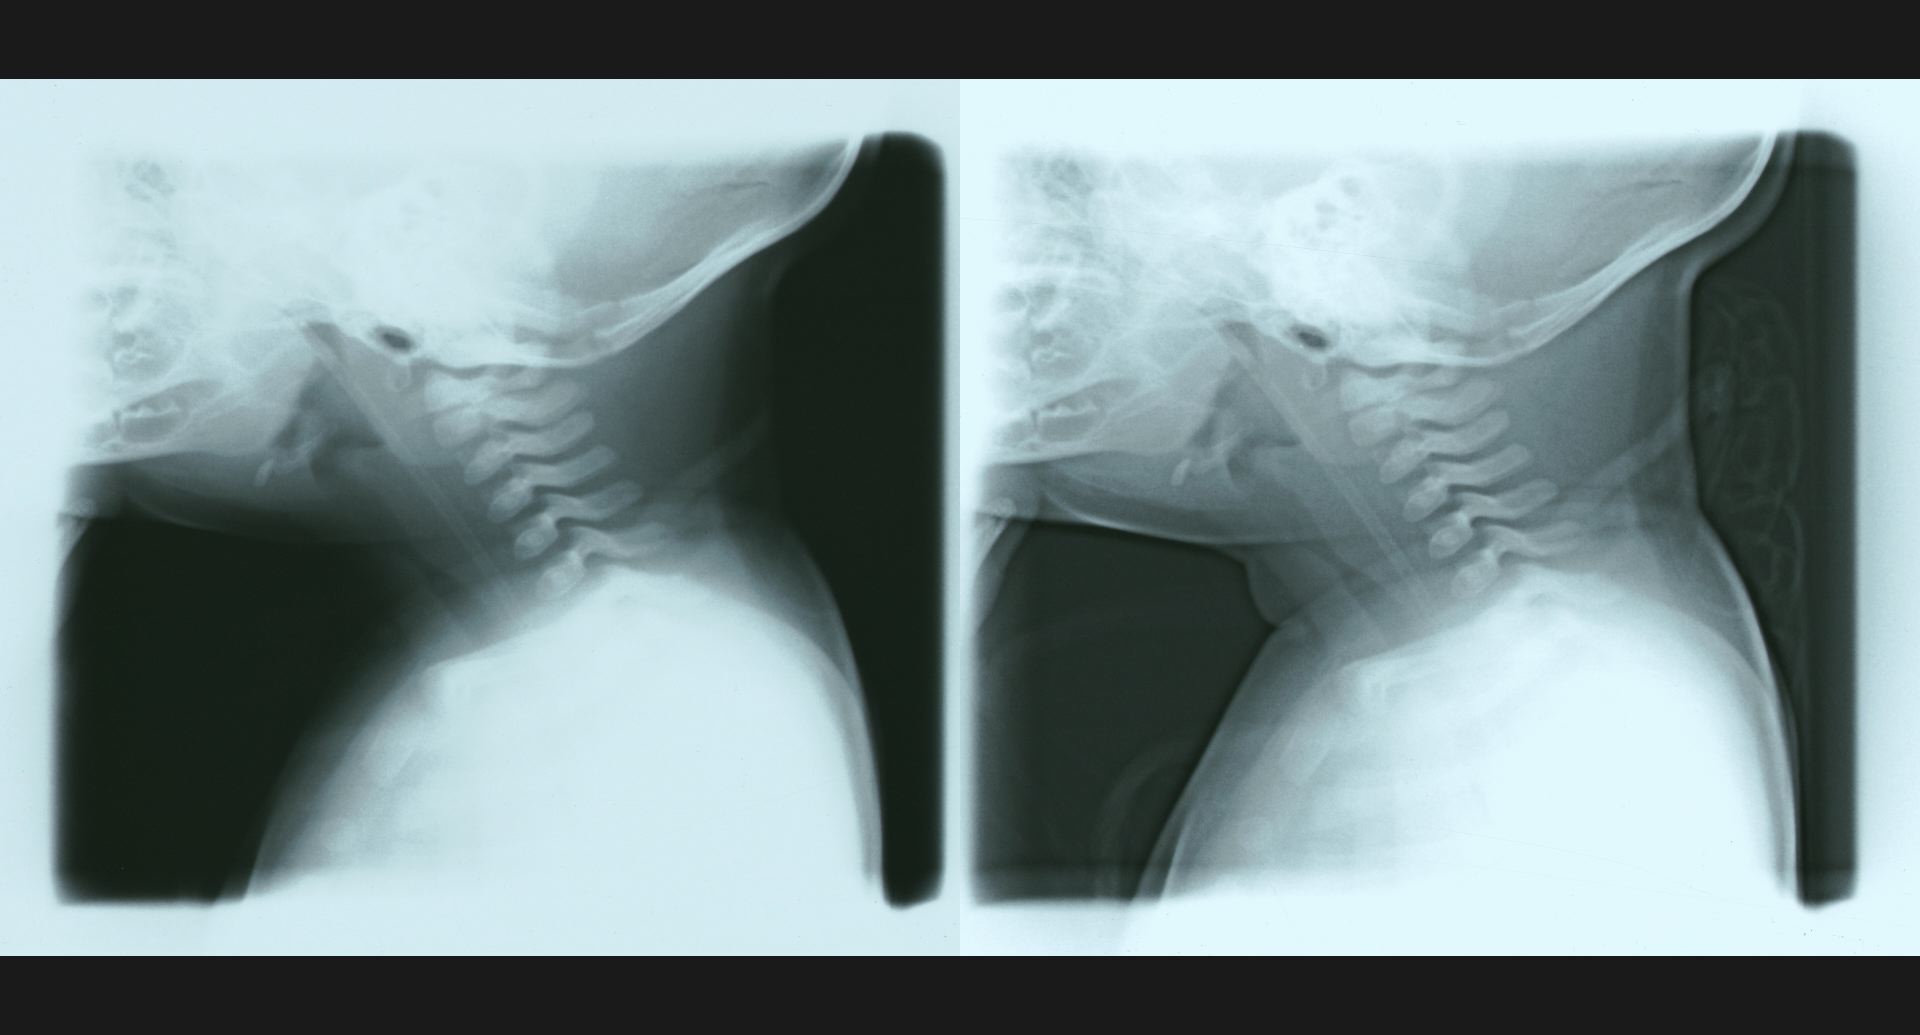

fig.2(104KB) :気胸